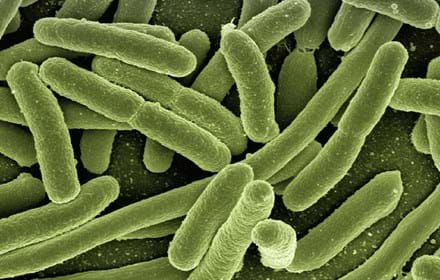

Kan snälla bakterier motverka typ 1-diabetes?

Oväntad koppling mellan virus och typ 1-diabetes